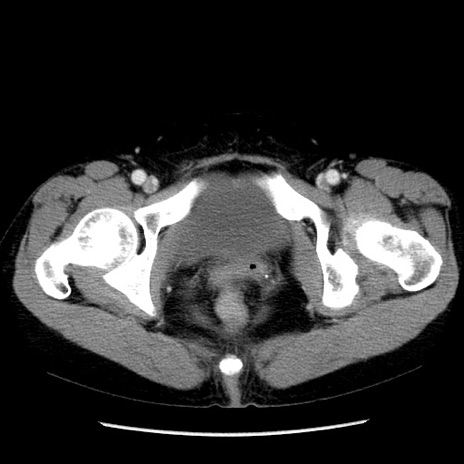

症例6(横断像)

【症例】50歳代女性

【主訴】下腹部痛

【現病歴】本日朝より下痢2回あり。 昼食を食べた後、嘔吐3回、下腹部痛認め、症状軽快せず、当院救急搬送。

【既往歴】卵巣癌術後(8年前に当院で卵巣摘出)

【身体所見】 意識清明、腹部:平坦、腸蠕動音→、やや硬、下腹部自発痛・圧痛あり、反跳痛あり、筋性防御なし。

【データ】WBC 16000、CRP 0.01